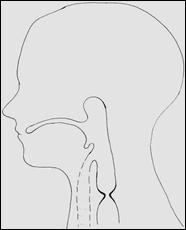

Рис. 10. Короткая шейная стриктура (схема) и вариант операции – циркулярная резекция пищевода с короткой шейной стриктурой.